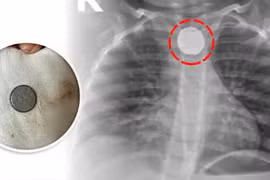

Dị vật đường tiêu hoá nếu không được phát hiện sớm và điều trị sẽ gây ra các nguy cơ chảy máu, thủng ruột, tắc ruột, áp xe ổ bụng, nghiêm trọng hơn có thể gây nhiễm khuẩn huyết nguy hiểm đến tính mạng.